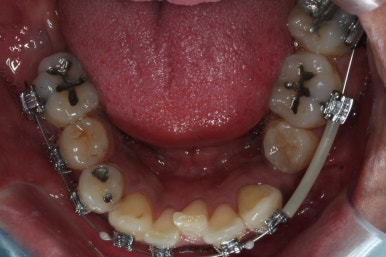

치료 시작 3개월째의 모습입니다.

서서히 가지런해지는 느낌이 드시나요?

화살표를 보면 작은 어금니 하나가 아래로 꺼져있는데, 이 녀석 때문에 애를 먹었네요. 훨씬 치료가 빨리 끝날 수 있었는데 이 치아가 워낙 잘 안움직이는 바람에 2년 개월정도로 치료기간이 많이 걸린 편이었어요.

치료 8개월째의 모습입니다.

이제 얼핏 보면 매우 가지런해졌어요. 이 뽑은 자리도 많이 남지 않았고 왼쪽 위 송곳니가 없지만 그리 표시도 많이 나지 않네요.

대신 위쪽 아래 작은 어금니가 애를 먹이고 있어요. 낚시줄처럼 부여매고 끌어올리는게 보이실거에요.

뼈에 단단히 붙어 안움직이는 경우를 "유착치아"라고 표현하는데, 유착치아라면 해당 치아를 움직이는 것을 포기했어야 했어요.

그래도 조금씩이라도 움직이고 있어서 계속 시도했습니다.